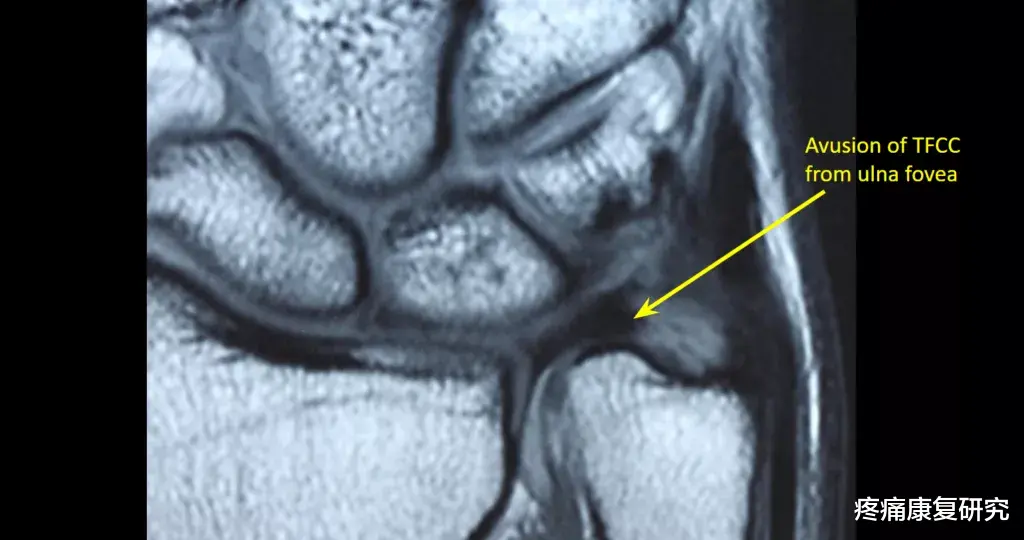

三角纤维软骨复合体(TFCC)是由一群纤维软骨与韧带组成的结构 , 位于腕关节内的尺侧(有小指的一侧) 。

- 它会帮助稳定桡尺远端关节(DRUJ)

- 为尺侧腕骨组织提供稳定度

- 能够吸收手腕20%的纵向冲击力

有些TFCC撕裂较小 , 稳定 , 可以通过保守治疗治愈 。 而另外一些TFCC撕裂较大 , 不稳定 , 可能需要手术干预 。